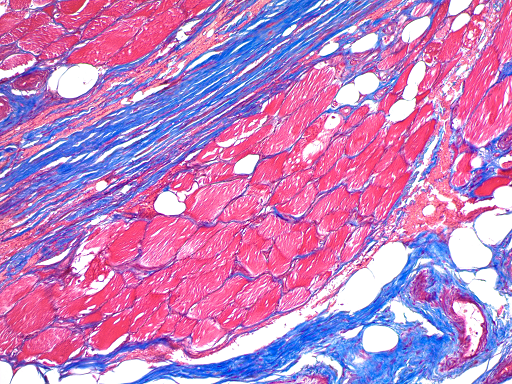

丽春红酸性品红-苯胺蓝染色,是用于检测动物组织中胶原纤维的一种染色方法之一,能够将胶原纤维染成蓝色,肌纤维、和红细胞呈红色,可用于鉴胶原纤维和肌纤维;并显示各种组织胶原纤维含量及纤维化程度。

胶原纤维呈天蓝色至亮深蓝色;肌纤维、胞质、纤维素、角质白呈红色至紫红色;红细胞呈水红色。